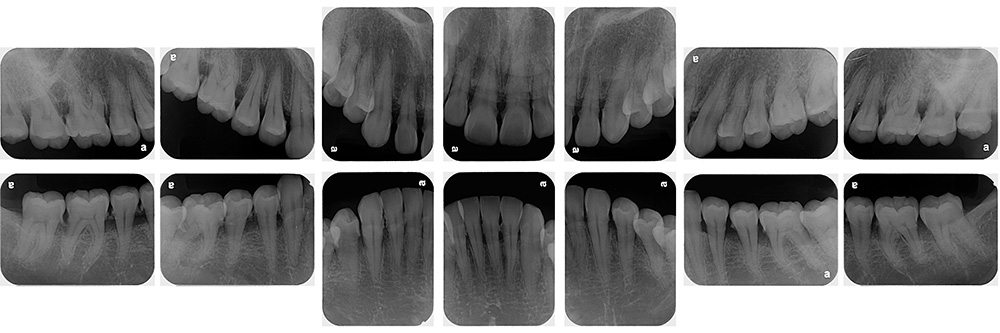

世代・性別

10歳女性

主訴

前歯が出ているのを治したい

治療内容

筋機能矯正治療(治療途中)

治療期間

4ヶ月

治療費

27万円(税別)

治療のリスク

歯の移動に伴う痛み